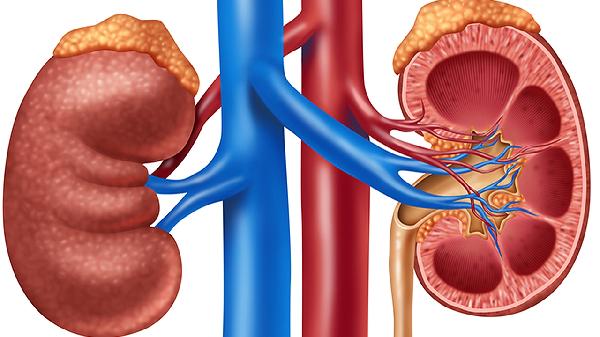

补肾防喘片中补骨脂、淫羊藿等成分能温补肾阳,适用于肾阳虚引起的腰膝冷痛、夜尿频繁。临床观察显示可改善肾上腺皮质功能,调节下丘脑-垂体-靶腺轴,需注意阴虚火旺者慎用。